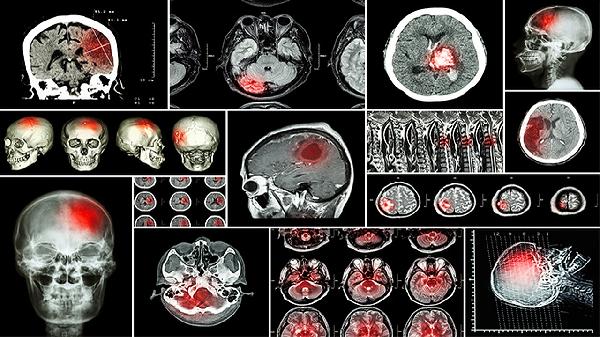

脑瘤能治好吗

脑瘤是否能治好应根据具体情况决定,如果病情较轻、治疗及时,通常能治好,如果病情严重、治疗不及时,通常不能治好,一旦患病,建议立刻就医,以免延误病情。1、通常能治好: 脑瘤是原发于颅内组织的肿瘤及脑转